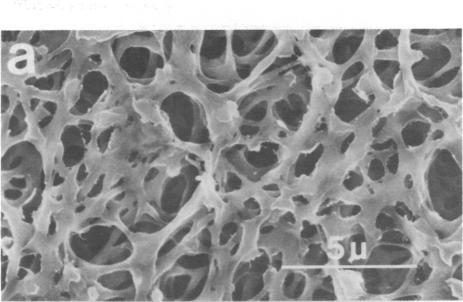

We covalently linked to regenerated cellulose filters a high-affinity monoclonal IgM produced against epitopes that reside on hepatitis B viral surface antigen (HBsAg). Conditions were established whereby as much as 250 micrograms of anti-HBsAg IgM could be linked to 2-4 mg of regenerated cellulose acetate by using cyanogen bromide and trichloro-s-triazine coupling agents. The immunoreactivity of the monoclonal anti-HBsAg IgM was preserved, and quantitative binding studies with HBsAg suggests that more than one functional binding site on the IgM molecule was operative. The specificity of the monoclonal anti-HBsAg IgM was established by demonstrating that a nonspecific monoclonal IgM (against influenza hemagglutinin), when coupled to the filters under identical conditions, had no effect on removal of HBsAg from serum. Most importantly, the monoclonal anti-HBsAg IgM-coupled filters quantitatively removed low levels of HBsAg from serum; after the third pass through the filter, HBsAg was undetectable in the perfusate. Further, the stability of the covalent bond between the anti-HBsAg IgM and regenerated cellulose acetate was shown by the lack of detectable murine monoclonal anti-HBsAg IgM in filtered serum despite 50 passages through the filter. Thus, we have demonstrated that monoclonal IgM antibodies with predefined specificity, when coupled to a biocompatible solid-phase support, may serve as a high-affinity and specific immunoabsorbant for quantitative removal and recovery of viral antigens from human serum. By using this approach, specific removal and recovery of many other substances from serum or plasma would seem possible.

我们将针对乙型肝炎病毒表面抗原(HBsAg)表位产生的高亲和力单克隆IgM共价连接到再生纤维素滤膜上。通过使用溴化氰和三氯-s-三嗪偶联剂,建立了条件,使得多达250微克的抗HBsAg IgM能够与2 - 4毫克的再生醋酸纤维素相连。单克隆抗HBsAg IgM的免疫反应性得以保留,并且与HBsAg的定量结合研究表明IgM分子上不止一个功能性结合位点起作用。单克隆抗HBsAg IgM的特异性通过以下方式得以确立:证明在相同条件下与滤膜偶联的非特异性单克隆IgM(针对流感血凝素)对从血清中去除HBsAg没有影响。最重要的是,单克隆抗HBsAg IgM偶联的滤膜能够从血清中定量去除低水平的HBsAg;在滤液第三次通过滤膜后,灌注液中检测不到HBsAg。此外,尽管滤液通过滤膜50次,但滤过血清中未检测到可检测到的鼠单克隆抗HBsAg IgM,这表明抗HBsAg IgM与再生醋酸纤维素之间的共价键具有稳定性。因此,我们已经证明,具有预定义特异性的单克隆IgM抗体,当与生物相容性固相支持物偶联时,可作为一种高亲和力和特异性的免疫吸附剂,用于从人血清中定量去除和回收病毒抗原。通过使用这种方法,从血清或血浆中特异性去除和回收许多其他物质似乎是可能的。